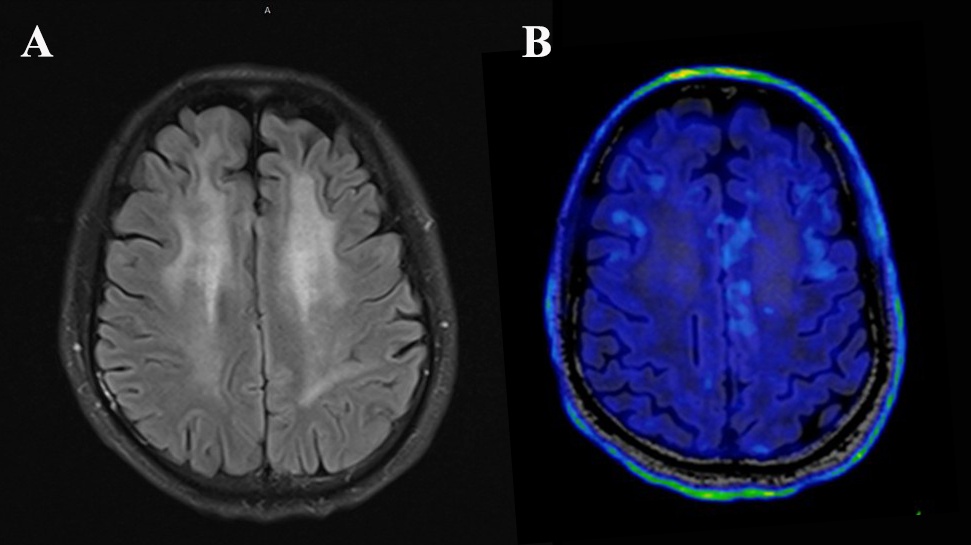

图2 治疗后,“白”脑逐渐恢复正常,炎症逐渐消退(绿色区域消失)。

复查影像也显示,曾经变“白”的大脑也在快速恢复,炎症核磁发现炎症范围大幅缩小。如今,回归工作岗位的李先生感慨:"感谢陈主任医疗团队,他们不仅治病,更重建了我的人生。"